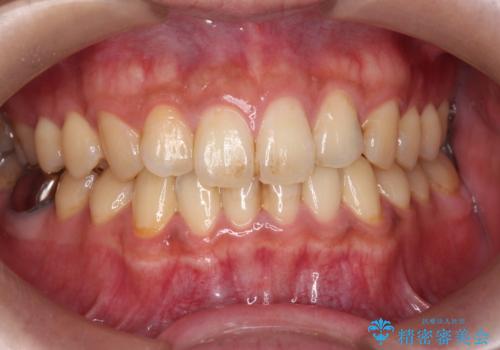

奥歯の着色が気になる セラミック治療

担当医 菊地俊介